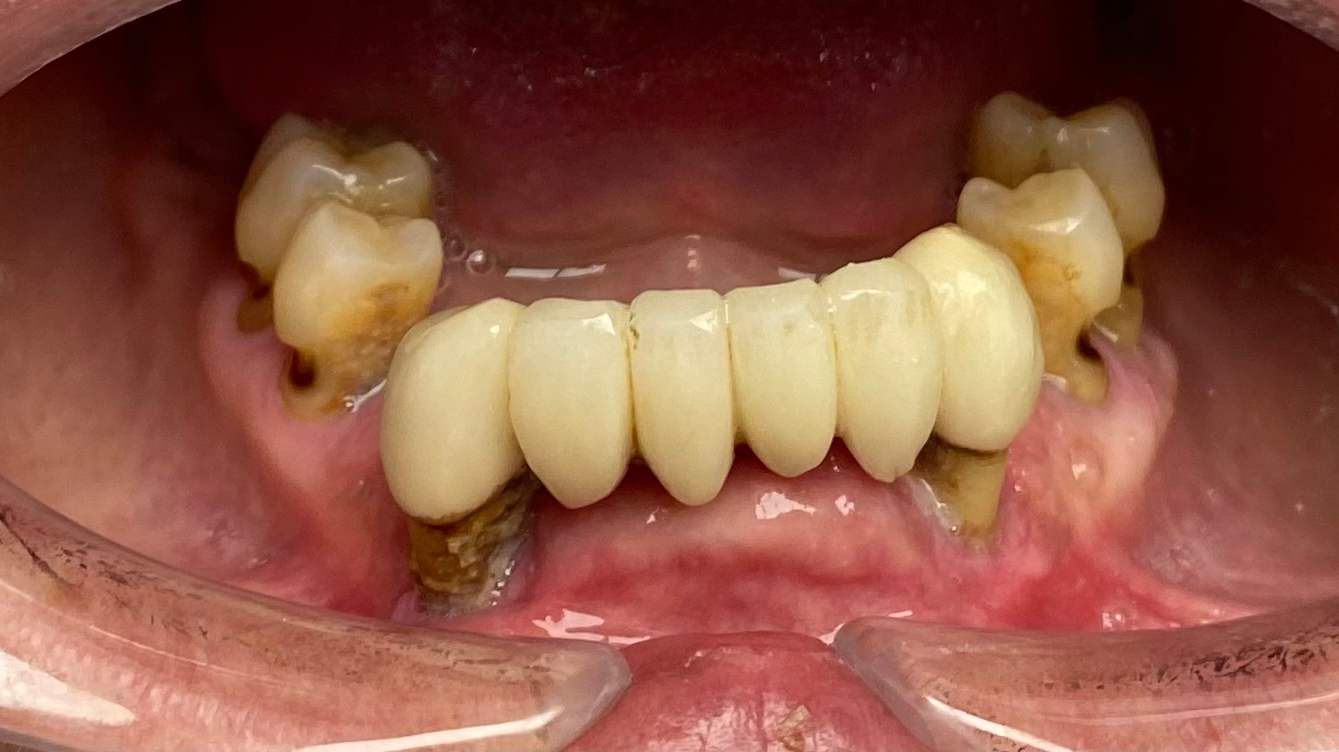

The signs and symptoms of addiction are well-known and include rampant caries (figure 1), especially smooth surface and anterior interproximal lesions, fractured teeth from bruxism and clenching, and gum disease from oral hygiene neglect.5 The acidic nature of these drugs combined with the xerostomia they cause can create unexplained and rapid deterioration of teeth, which is one of the hallmarks of drug use.

In addition, carriers of these drugs such as Actiq (fentanyl in a lozenge used in the transmucosal form in the mouth) can contain high doses of sugar, further exacerbating a bad situation. Even drugs used to combat the pleasurable effects of opioids by making them less appealing, such as buprenorphine (Suboxone), have recently been flagged by the FDA as drugs that can result in dental disease. These drugs have a low pH (3.4) and are designed to be placed sublingually or on the mucosa of the cheek and dissolve in the mouth for 10 minutes.

This type of contact can result in caries along the cervical region of the tooth as well as gum and tissue problems.6 Unrestorable caries and/or gum disease can often lead to tooth extraction (figure 2) and, once the addiction is controlled, the need for dentures or dental implants.